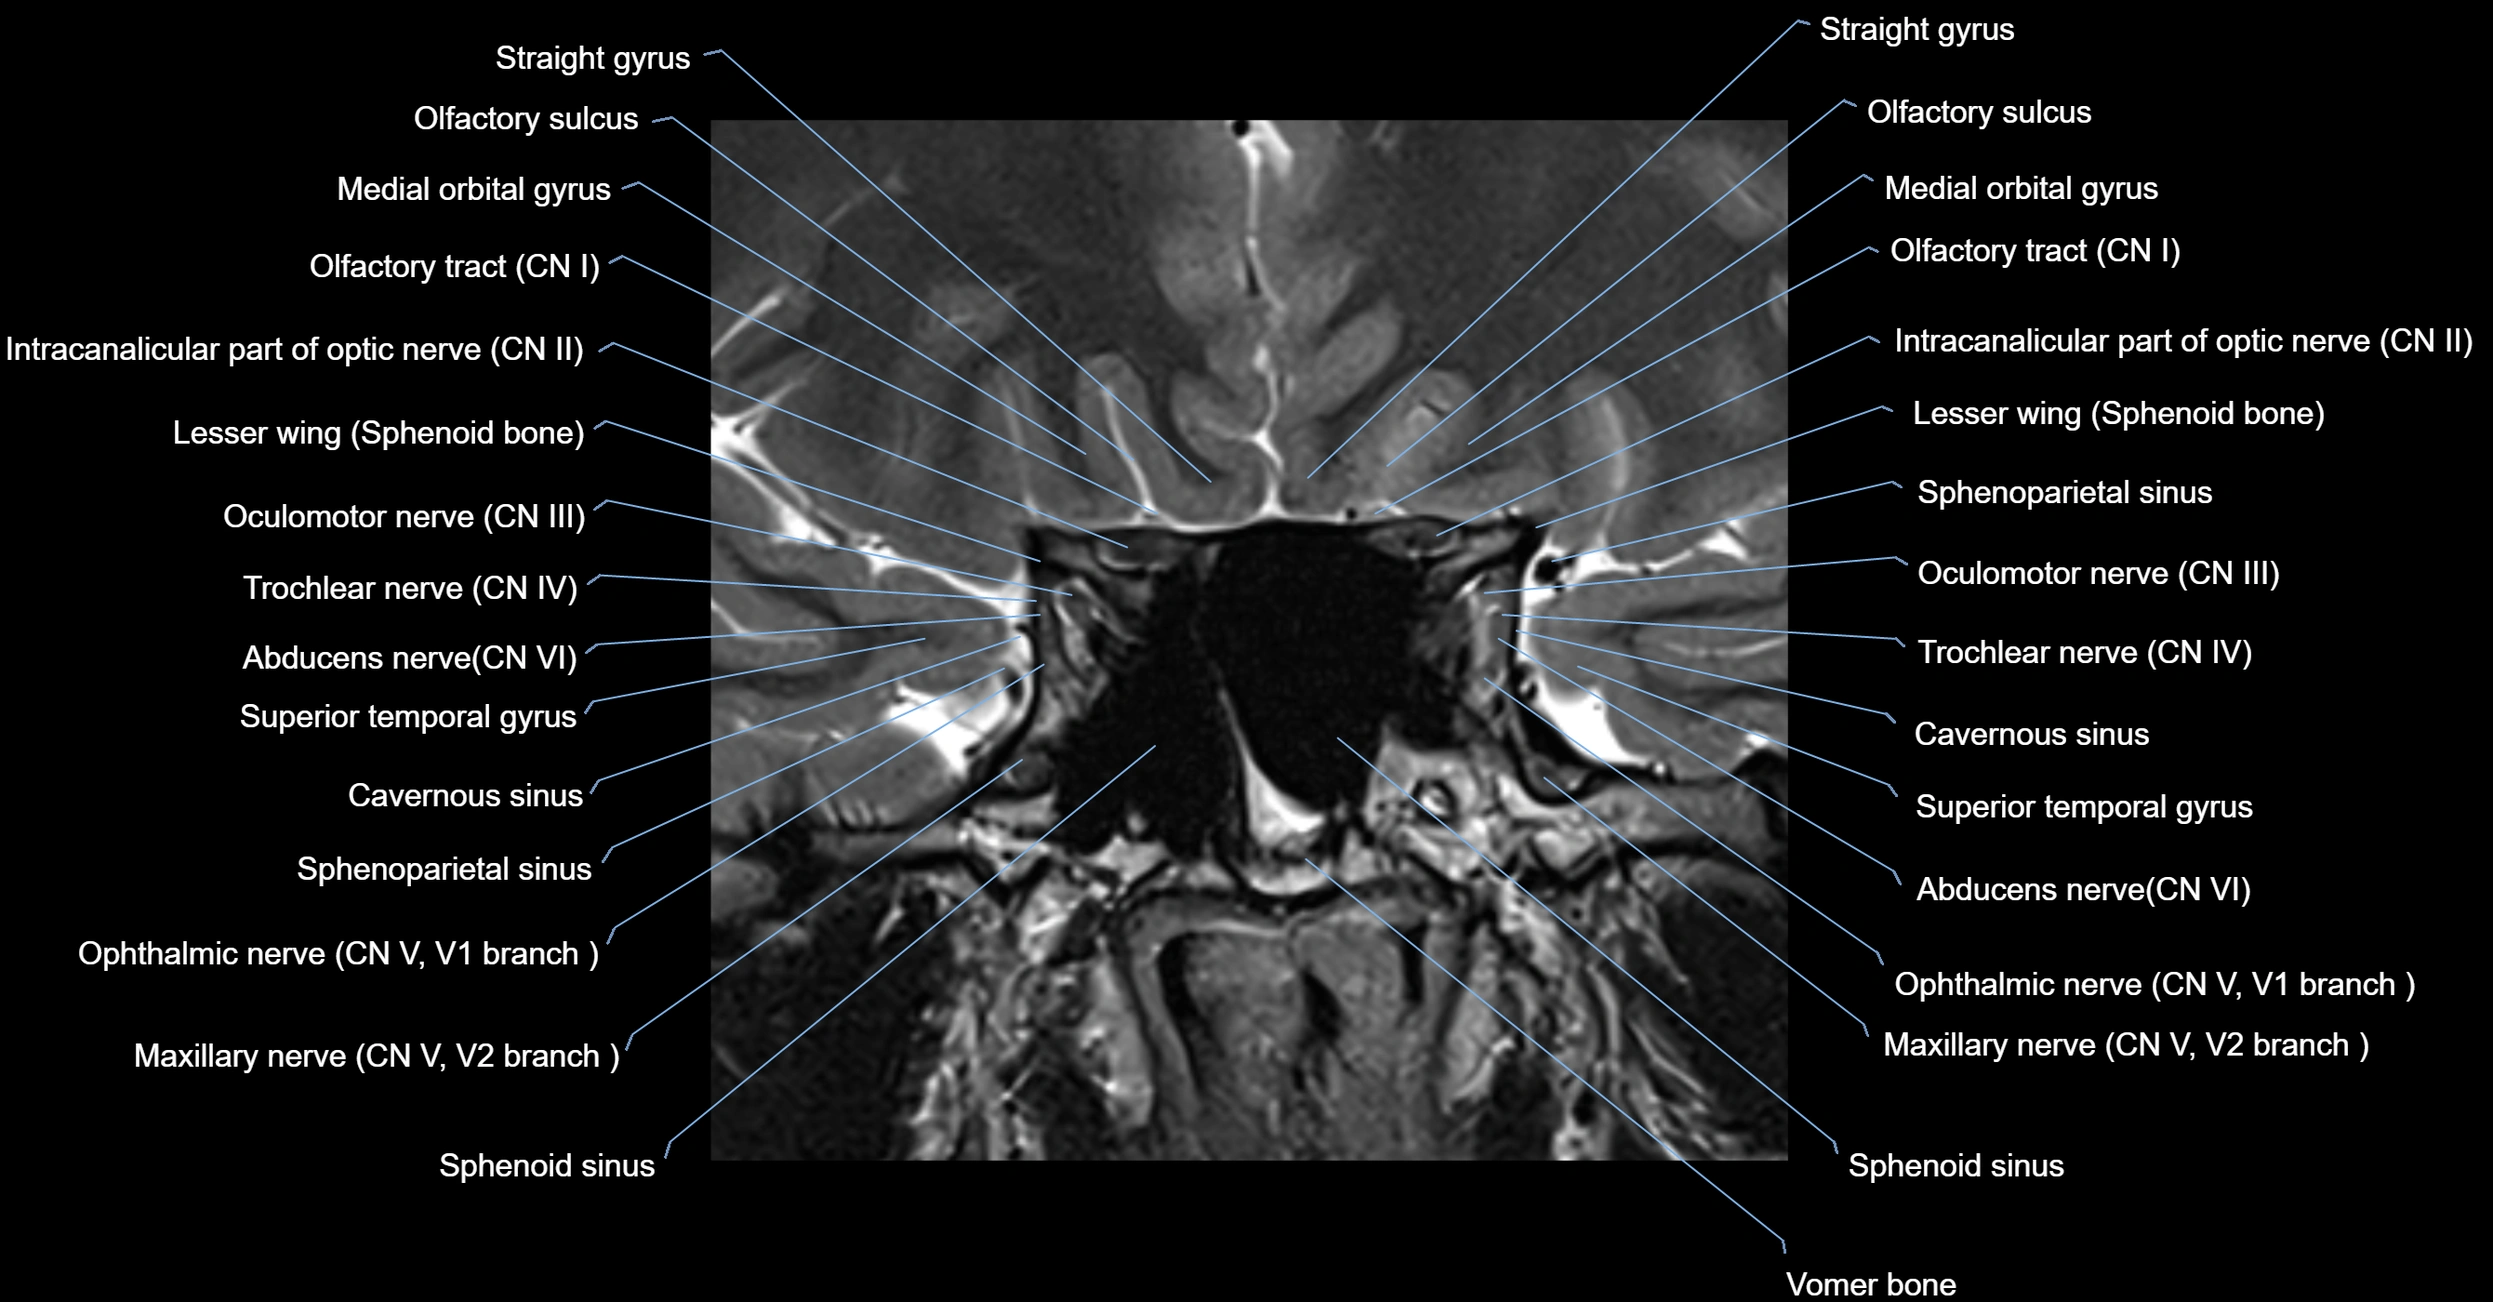

MRI Appearance

The abducens nerve is a small, thin, linear structure

Best visualized on high-resolution T2-weighted 3D MRI sequences (e.g., FIESTA or CISS)

Seen as a hypointense (dark) line running from the brainstem at the pontomedullary junction, traversing the prepontine cistern, and entering Dorello’s canal under the petrosphenoidal ligament, then into the cavernous sinus, and finally the orbit

May be challenging to visualize in standard MRI due to its small size

Pathology may be inferred by absence, displacement, or enhancement of the nerve